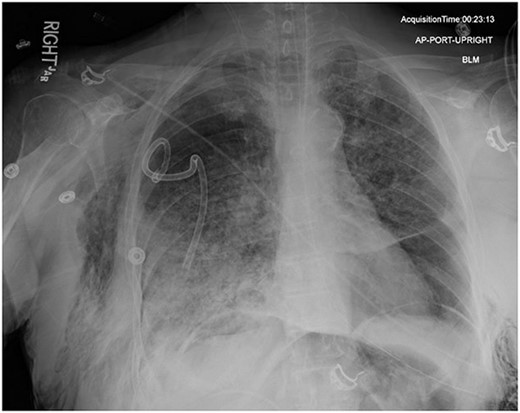

On Hospital Day 2, an interval CXR showed continued resolution of the right-sided pneumothorax but worsening subcutaneous emphysema of the bilateral chest wall and pneumoperitoneum (Fig. 3). Surgical consultation was sought, leading to diagnostic laparoscopy. In the abdomen, emphysematous changes within the gastrohepatic ligament and omental adhesions to the anterior abdominal wall were visualized (Figs 5 and 6). Laparoscopic exploration revealed no diaphragmatic injury or perforated viscera but identified emphysematous changes throughout the preperitoneal space, small and large bowel mesentery, and right paracolic gutter (Figs 7 and 8). Immediate post-op CXR no longer showed evidence of pneumoperitoneum (Fig. 4). The patient was transferred back to the ICU and extubated after three days on Day 5. After the removal of chest tube and transfer to a medical floor on Day 8, the patient developed aspiration pneumonia that was treated with antibiotics. She was discharged on Day 15.

AP upright chest radiograph showing intraabdominal free air, right-sided chest tube in place, and bilateral chest wall subcutaneous emphysema that is worse on the right. Bilateral patchy airspace disease is noted as well.